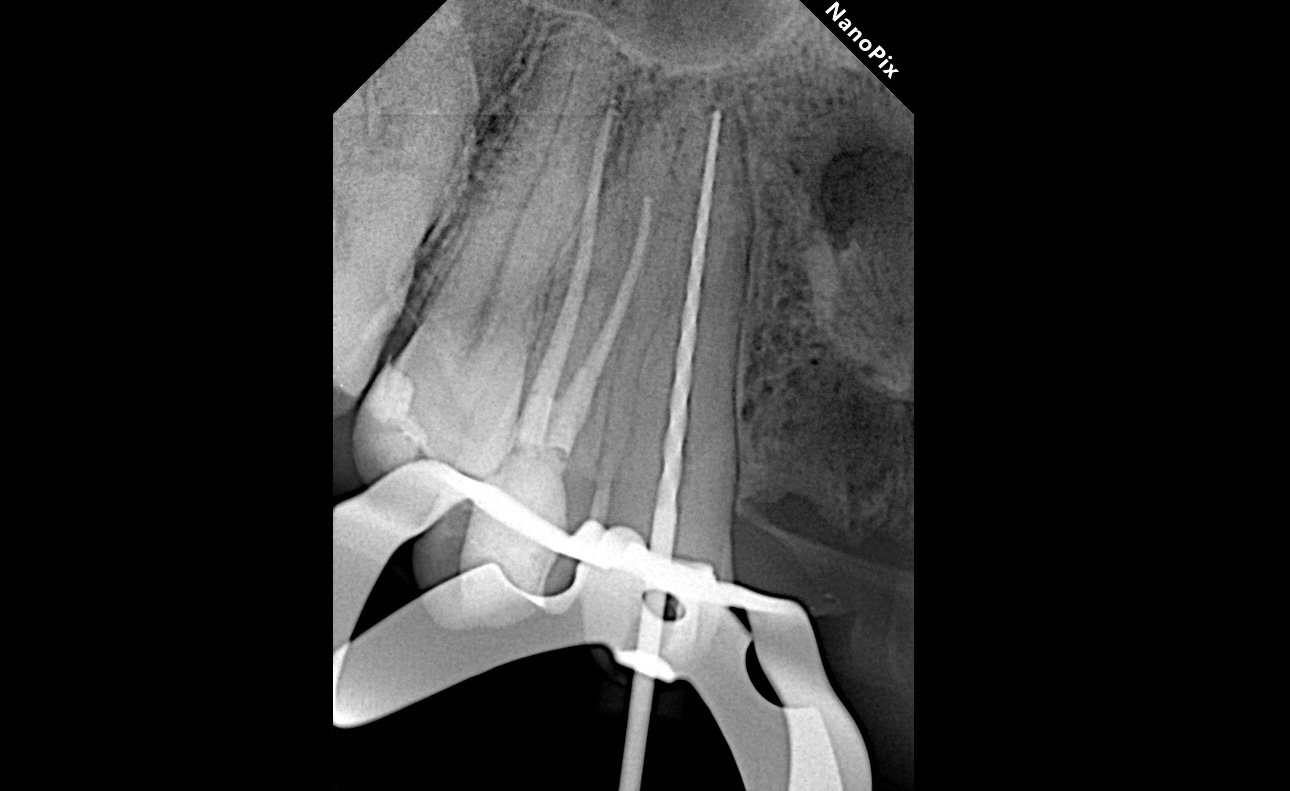

Дезобтурация Sani retreatment. Важно работать от корональной трети, постепенно двигаясь в апикальном направлении. Не стремиться сразу пройти на всю длину канала.

Инструментация Soco SC до 45/04. Финишный инструмент до чистых опилок на кончике файла.

Ирригация 3% NaOCl с УЗ активацией + 17% ЭДТА.

Обтурация биокерамическим силером с гуттаперчей. Автор: Диана Кипарисова